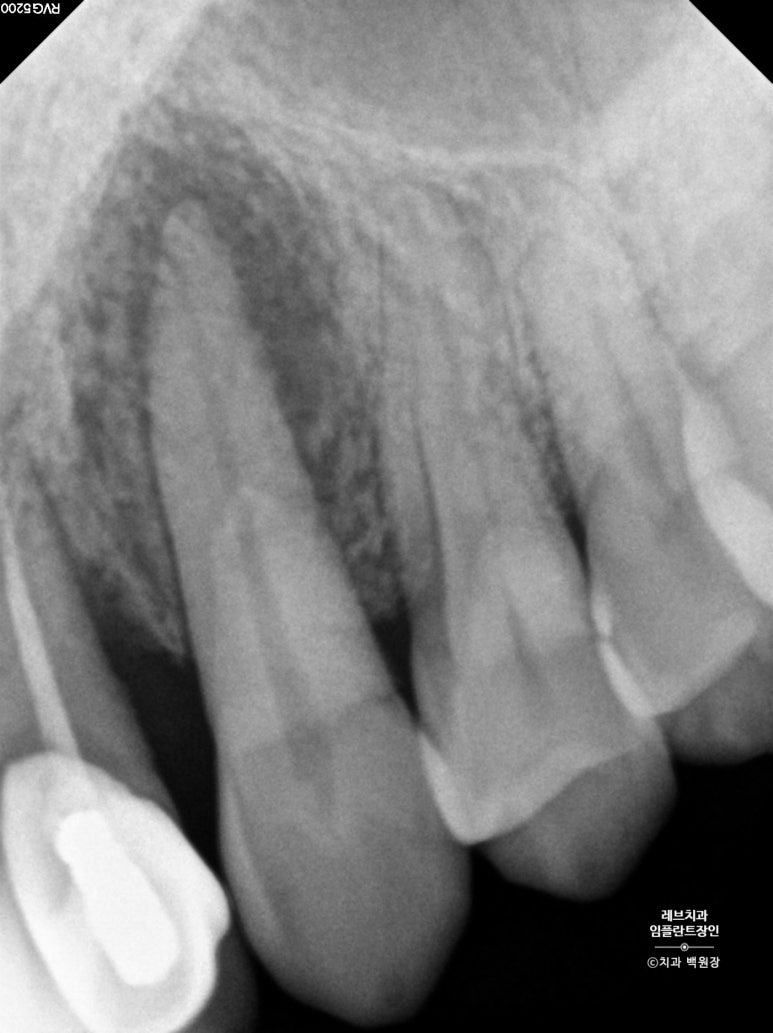

확대해볼 수 있는 치근단 방사선 사진을 보시면, 송곳니 뿌리 주변으로 거무딩딩하게 뼈가 없어진 것을 보실 수 있습니다.

만성치주염으로 상당히 많은 양의 잇몸뼈가 파괴되었죠.